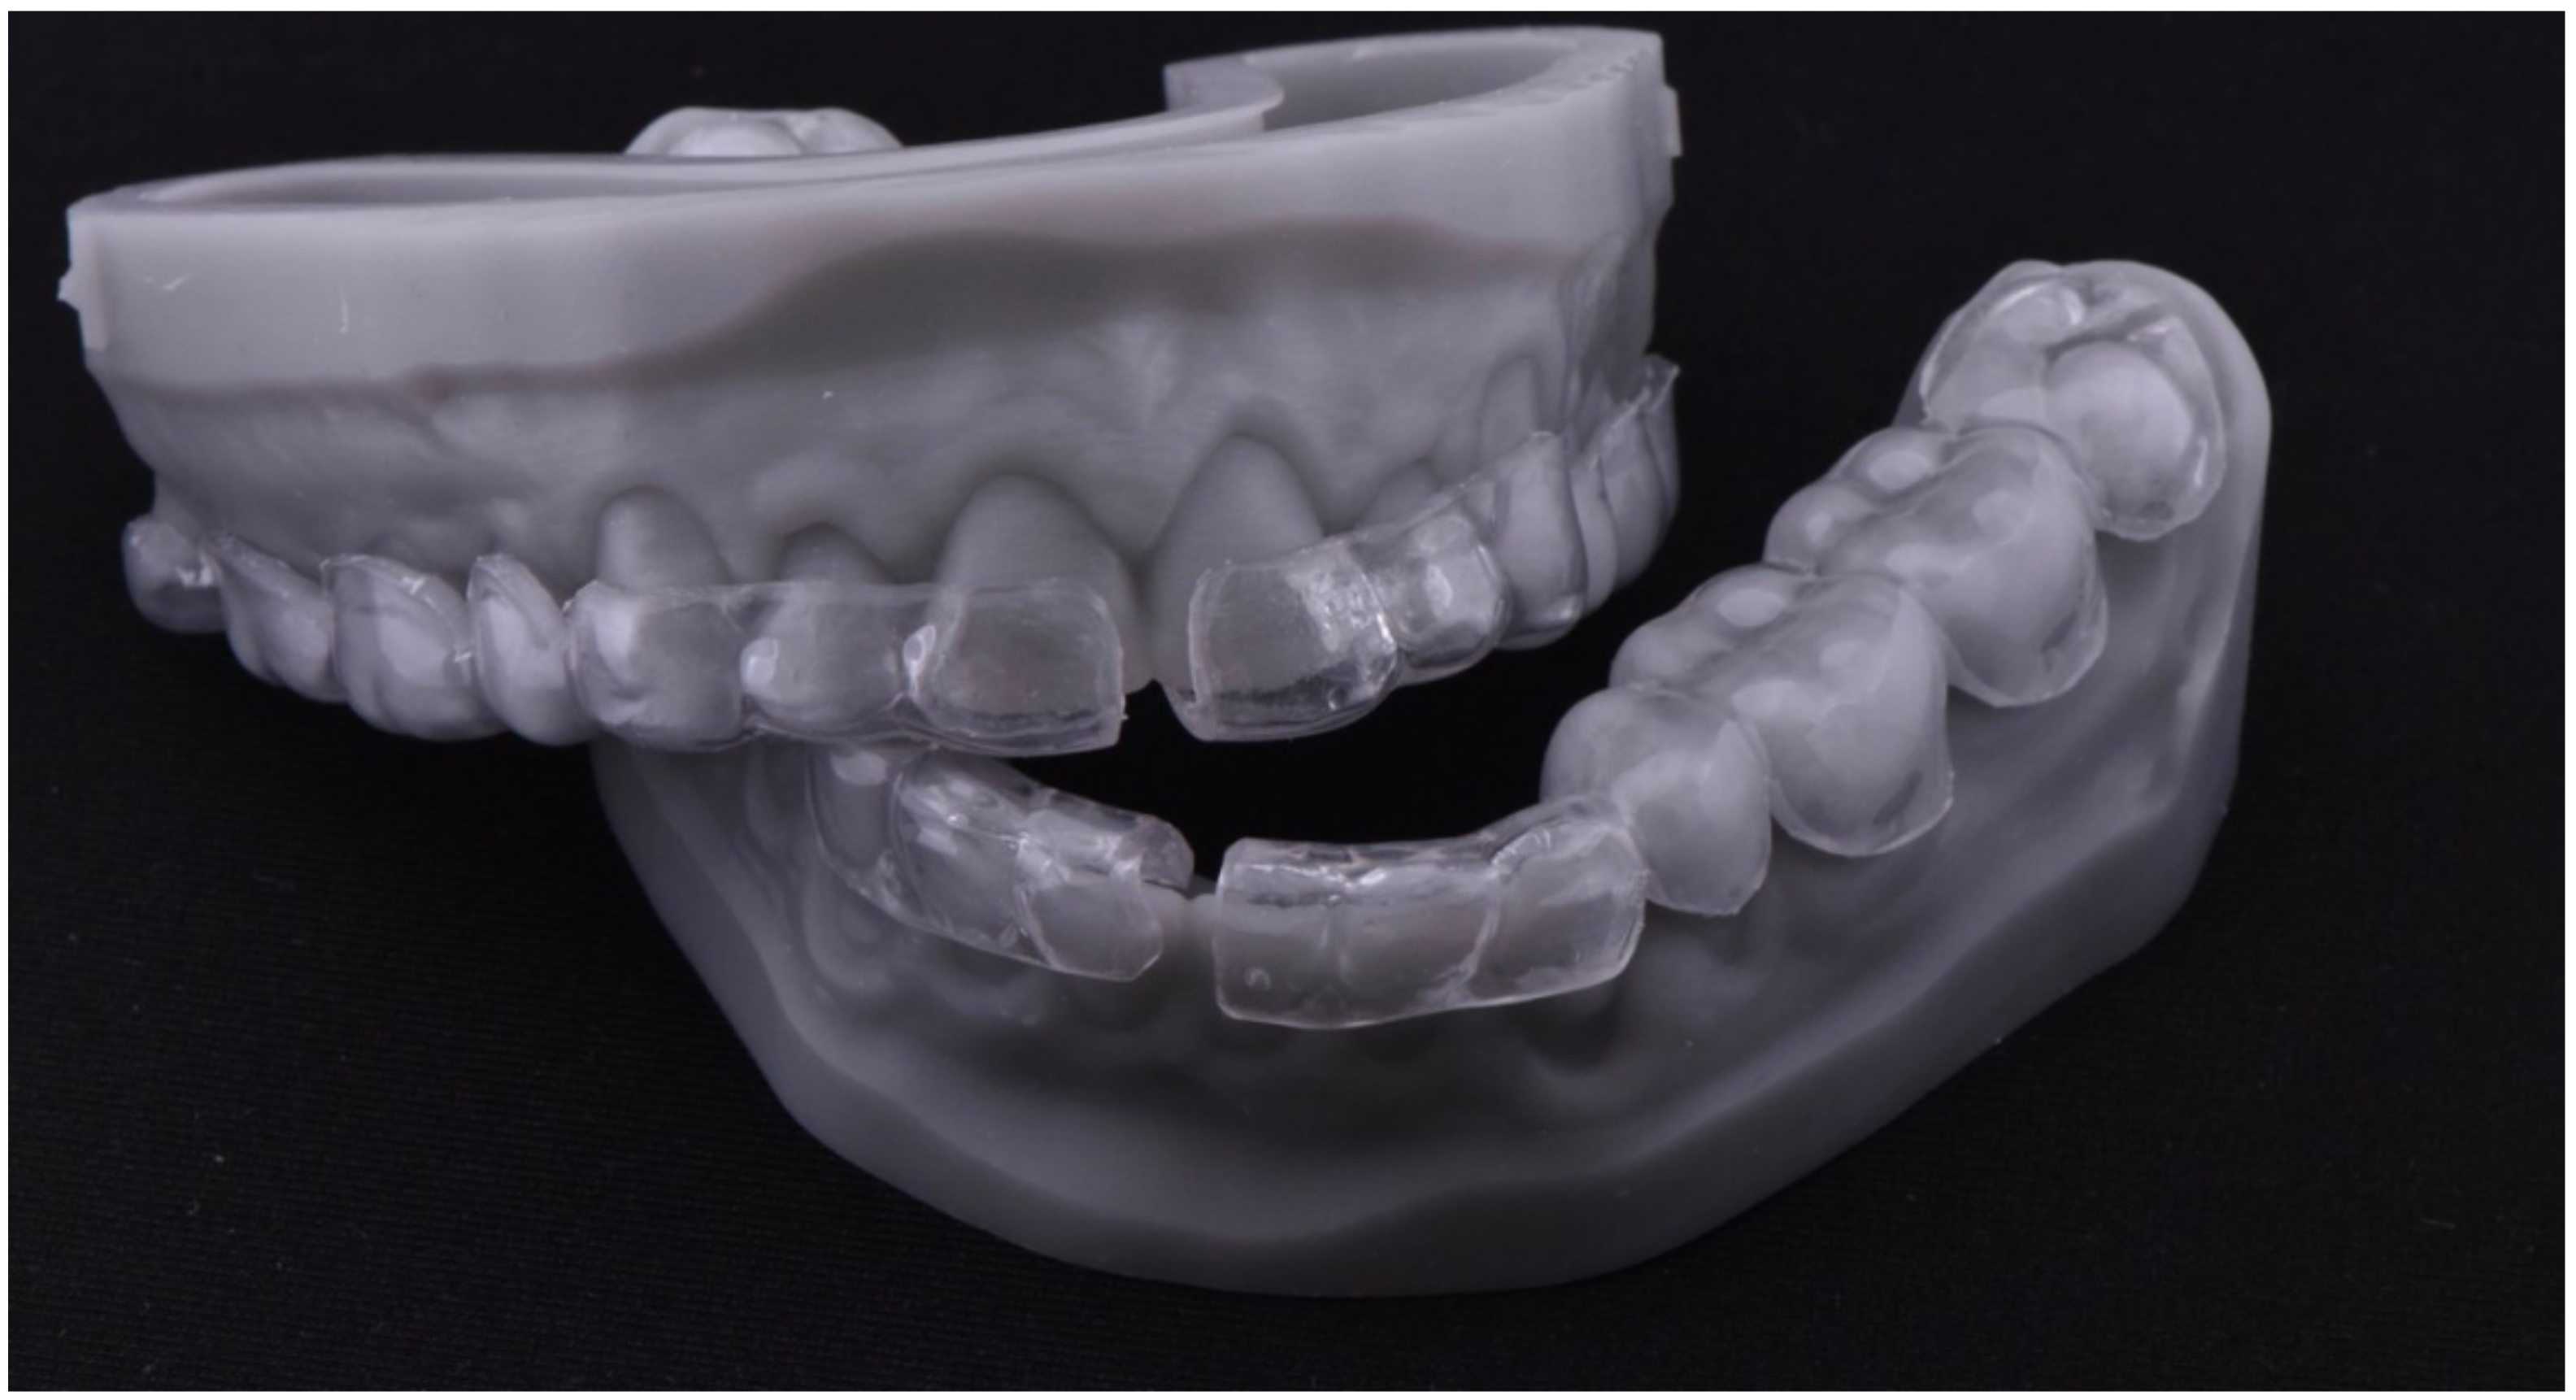

2.1. Planning Phase

2.2. Restorative Phase